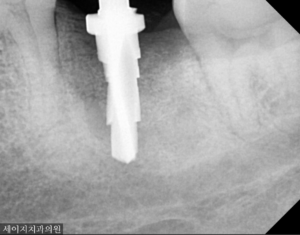

2023. 5. 4(초진 시 발견된 광범위한 골소실)

먼저 X-ray 장비를 이용하여 해당부위를 관찰하였습니다. 예상대로, 치아의 뿌리쪽에 염증이 생겨 있었으며 광범위한 상태의 골소실이 관찰되었습니다.